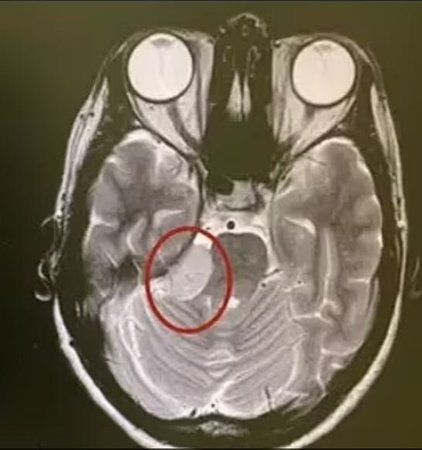

Kanada'nın Montreal eyaletinde yaşayan Anreea Vanacker adındaki bir kadına, yüzünün belli bir tarafında duyduğu ağrıların nedeninin, 10 senedir sessiz bir şekilde büyüyen biri beyin tümörü olduğu açıklandı. Doktorlar, ağrının kafatası içinde yer alan büyük, iyi huylu bir tümörün yüz kaslarını kontrol etmekten sorumlu olan sinire baskı yapmasından kaynaklanmış olduğunu söylerken Vanacker, yaşamış olduğu ağrının bir sabah uyarı vermeden ortaya çıktığını ve konuşmaya, gülmeye hatta yemek yemeye çalıştığı zamanda meydana geldiğini ifade etti.

Tümör, doktorların kafatasının bir kısmını çıkarmak ve beyni kesmek zorunda kaldıkları bir ameliyat sonrasında alındı. Tümörün tamamı çıkartıldı fakat kadının gücünü geri kazanmasının bir sene kadar zaman alacağı söylendi. Bir yönetim danışmanlığı firmasının üst düzey yetkilisi olan Vanacker, alkol ile kahveden uzak durmak, düzenli bir şekilde egzersiz yapmak ve her gece en az 7 saat uyumak gibi sağlıklı olan yaşam tarzıyla gurur duymuş olduğunu ifade etti. Bundan dolayı, 2020 yılının temmuz ayında vücudunda bir tümör olduğunu öğrenmek onun adına şok etkisi meydana getirdi. ‘Yüz kaslarımı her hareket ettirdiğim zaman yüzümün sağ tarafında elektrik çarpması gibi hissedilen yoğun bir ağrı vardı’ diyen Vanacker, soluğu doktorda aldı.